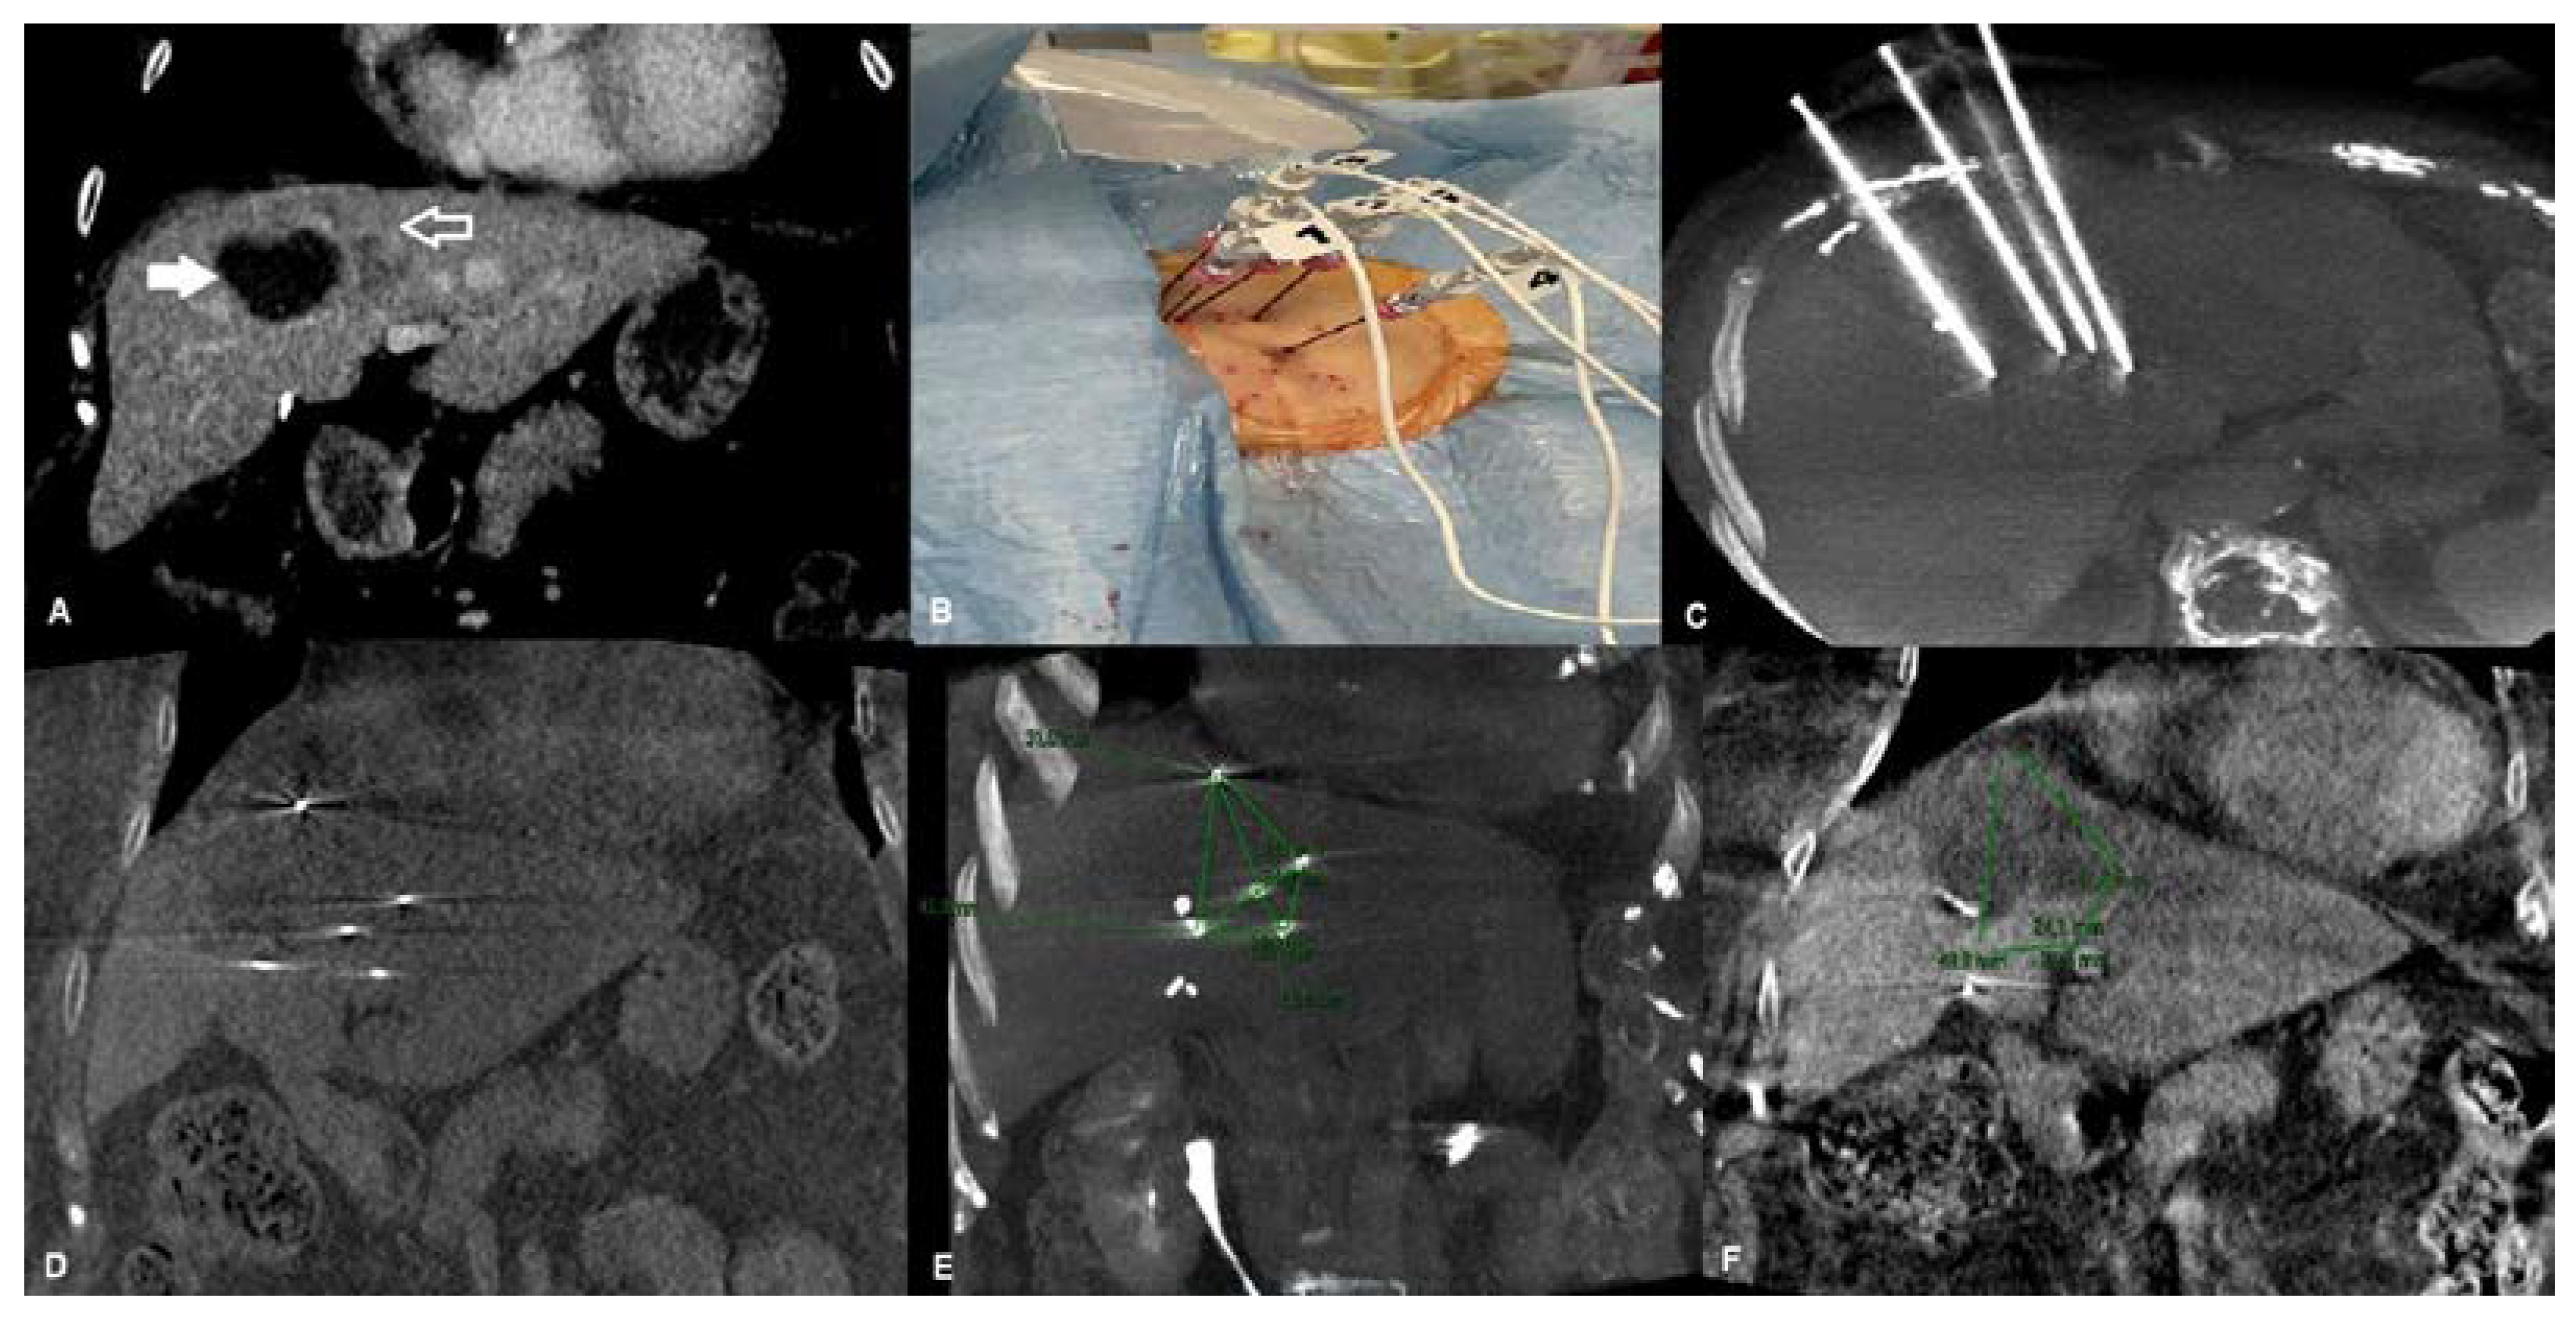

2.1. Procedural Steps